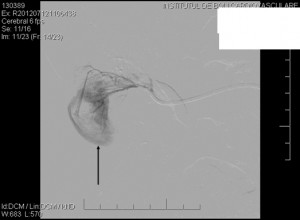

The patient was under observation on the cathlab floor during the next 60 minutes and after that the sheath was removed and hemostasis was achieved. She returned to her room but no longer then 15 minutes after she reported nausea, diaphoresis and weakness. Hypoglycemia was initially suspected but the glucotest showed a 260 mg/dl value of the serum glucose. The patient became hypotensive (systolic blood pressure 80 mm Hg) and soon after she complained of increasing pain in the right lumbar area. An ultrasound made at the bedside showed a right perirenal hematoma. The lab test indicated a dramatic decrease in the hemoglobin level, from 13 mg/dl to 8.0 mg /dl. The patient was practically in hemorrhagic shock. The decision was to transfer immediately the patient to the cathlab for an angiographic control. A new puncture of the right femoral artery was made, because the initial suspicion was an iliac rupture or perforation in the stent area, due to the extensive calcification of the arterial wall. The first injection of contrast media through the sheath showed that there was no problem with the stent. After that a global injection into the abdominal aorta, at the renal arteries level, was made, and a small effraction in the right renal parenchyma was observed (Figure 3). Selective intubation of the right renal artery was made with a JR 4.0 diagnostic catheter and that confirmed the source of bleeding in the right posterior segmental artery (Figure 4). Careful superselective intubation of this branch was performed (Figure 5), and small particles of gelatin sponge (Gelaspon) mixed with contrast media were delivered through the catheter. The embolization7 was successful in stopping the bleeding (Figure 6) but since there was about 20% of the renal parenchyma without vascularization and the patient still had important pain in the lumbar area, the decision was to transfer her to the urology department. A CT-scan (Figure 7) indicated a large subcapsular and retroperitoneal hematoma and also the presence of the contrast media in the urinary tract, an indication that the renal function was still preserved. In accordance with these findings, a renal lobectomy (partial nephrectomy) was performed, along with the evacuation of the hematoma. There was a parenchymal sparing intervention that preserved almost the entire kidney. The outcome was complicated by a pneumothorax after a central venous catheter insertion and by a right femoral hematoma following the two arterial punctures. However, after 14 days the patient was discharged in pretty good condition. One year later she has no claudication, the pulse in the right femoral artery is very good and the serum creatinine is normal.

Figure 5. Superselective intubation of the “guilty” segmental artery; arrow indicates the large subcapsular hematoma.